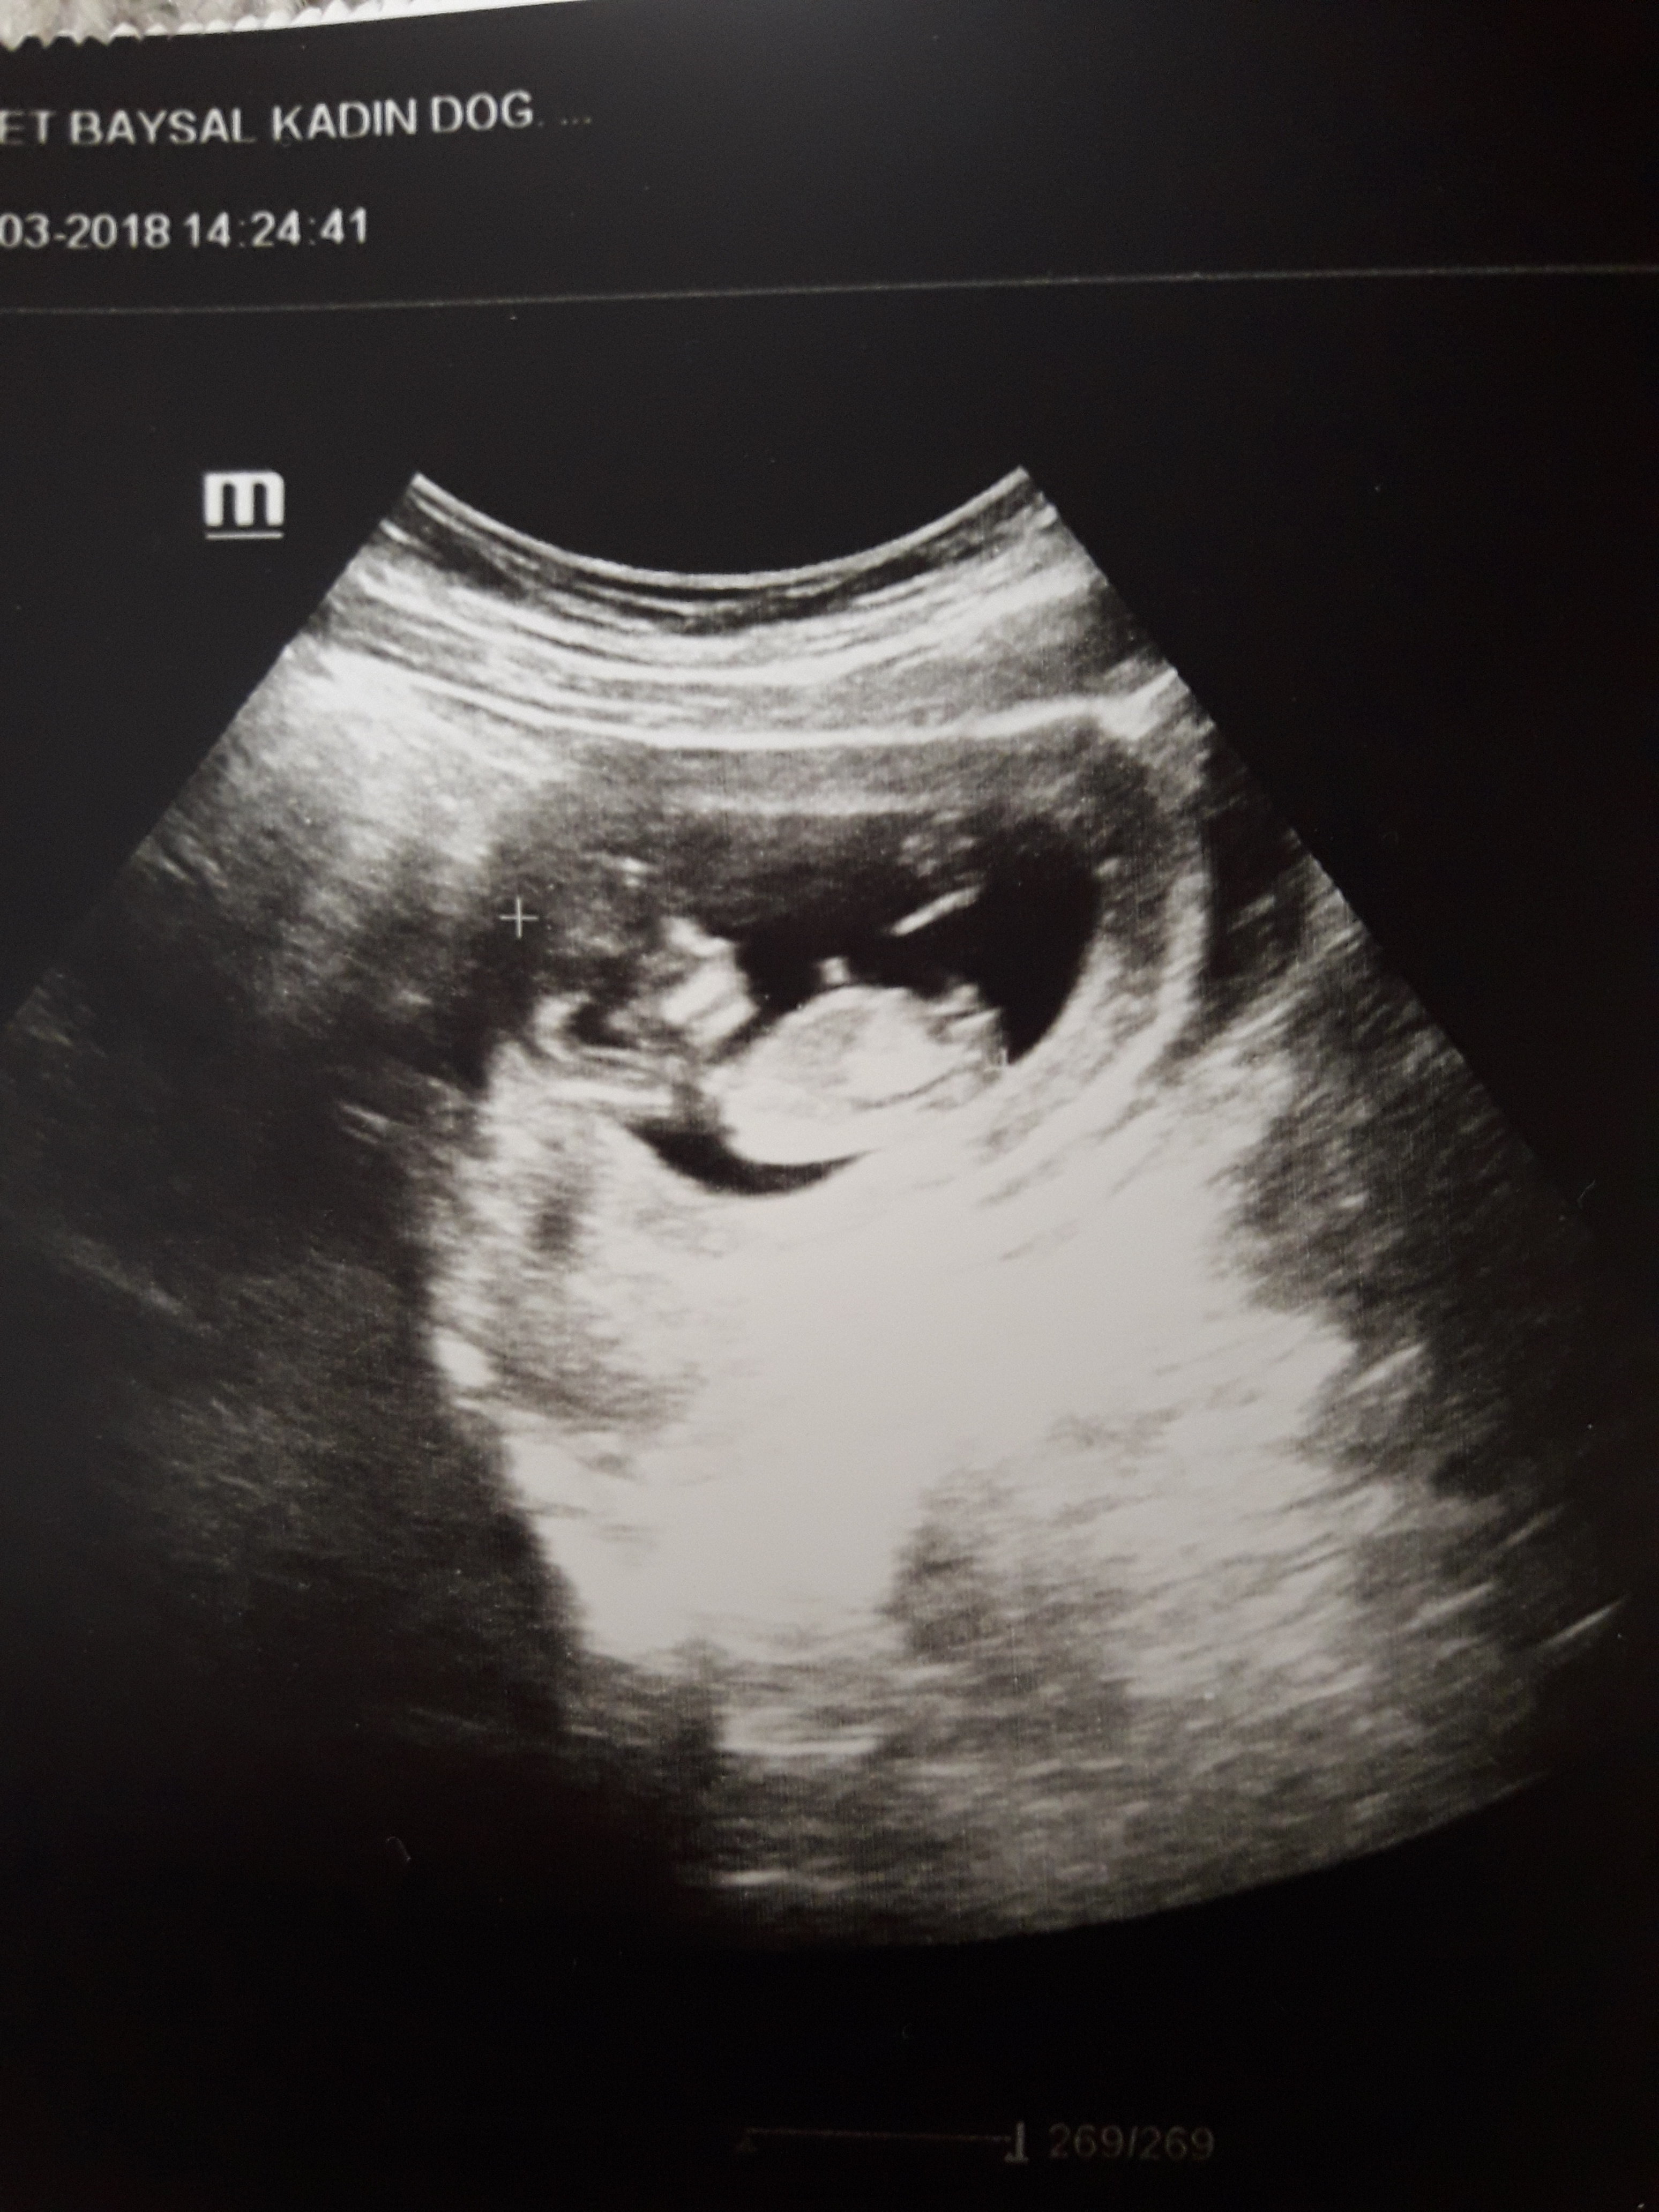

Resim pek net değil emin olmamakla birlikte bebeğinizin cinsiyetinin erkek olduğu kanaatindeyim. Bebeğinizin cinsiyetini 17-19 - 20. haftalarda net olarak öğrenebilirsiniz. Sağlıklı gebelik geçirmeniz dileği ile.

Gercekten mi. Birazda olsa yuregme su serptniz. Erkek cocugum olmasini cok istiyorum. Bu usg ye bakinca nub teorisinden dolayi kiza benzettim biraz icim burkulmustu. Peki nasil anladiniz erkek olduğunu cok merak ediyorum